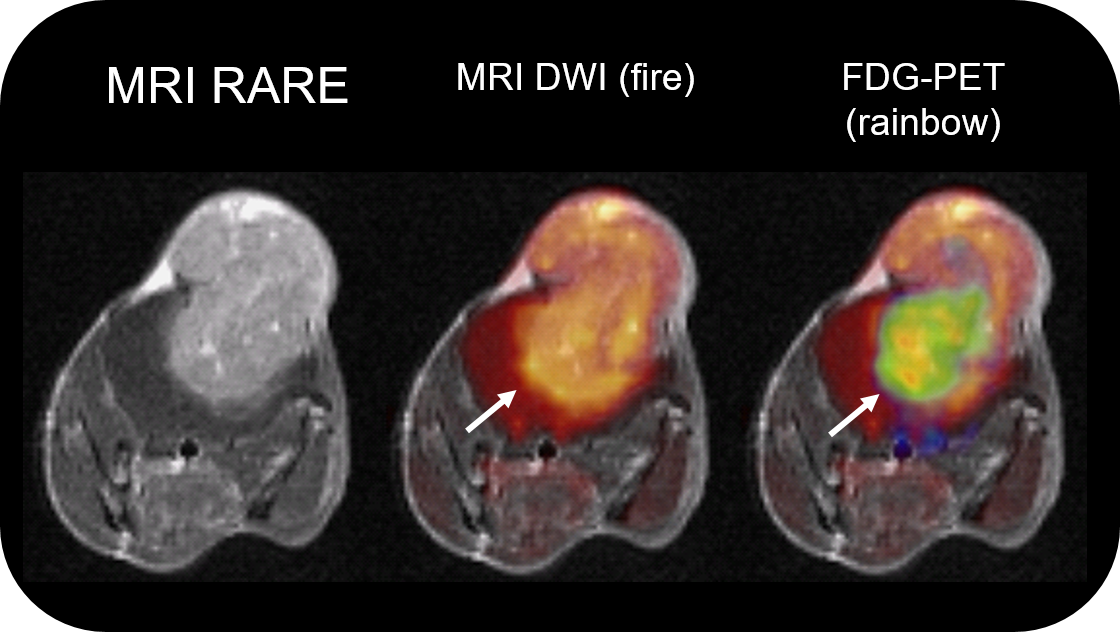

PET Insert or Inline

Upgradable with state-of-the-art PET module as inline or insert with full field of view and accuracy offers real, homogeneous sub-millimetric volumetric PET resolution and quantification in all three axes, in the entire field of view. This is possible due continuous crystal detectors with SiPM technology and true depth of interaction 3D precision equivalent to 10+ layer pixelated crystal detectors.